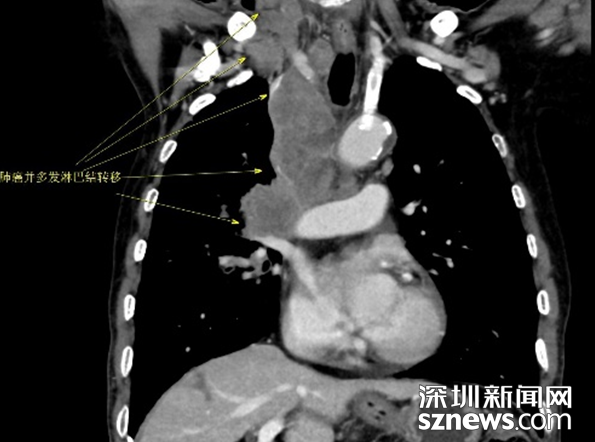

进一步CT增强提示右肺癌并多发淋巴结转移

李大爷在子女的陪同下来到中山七院胸外科复诊。通过进一步检查,确诊为右肺癌并胸膜转移,纵膈、腹膜后淋巴结转移。这一消息仿佛晴天霹雳,让全家人不敢相信。